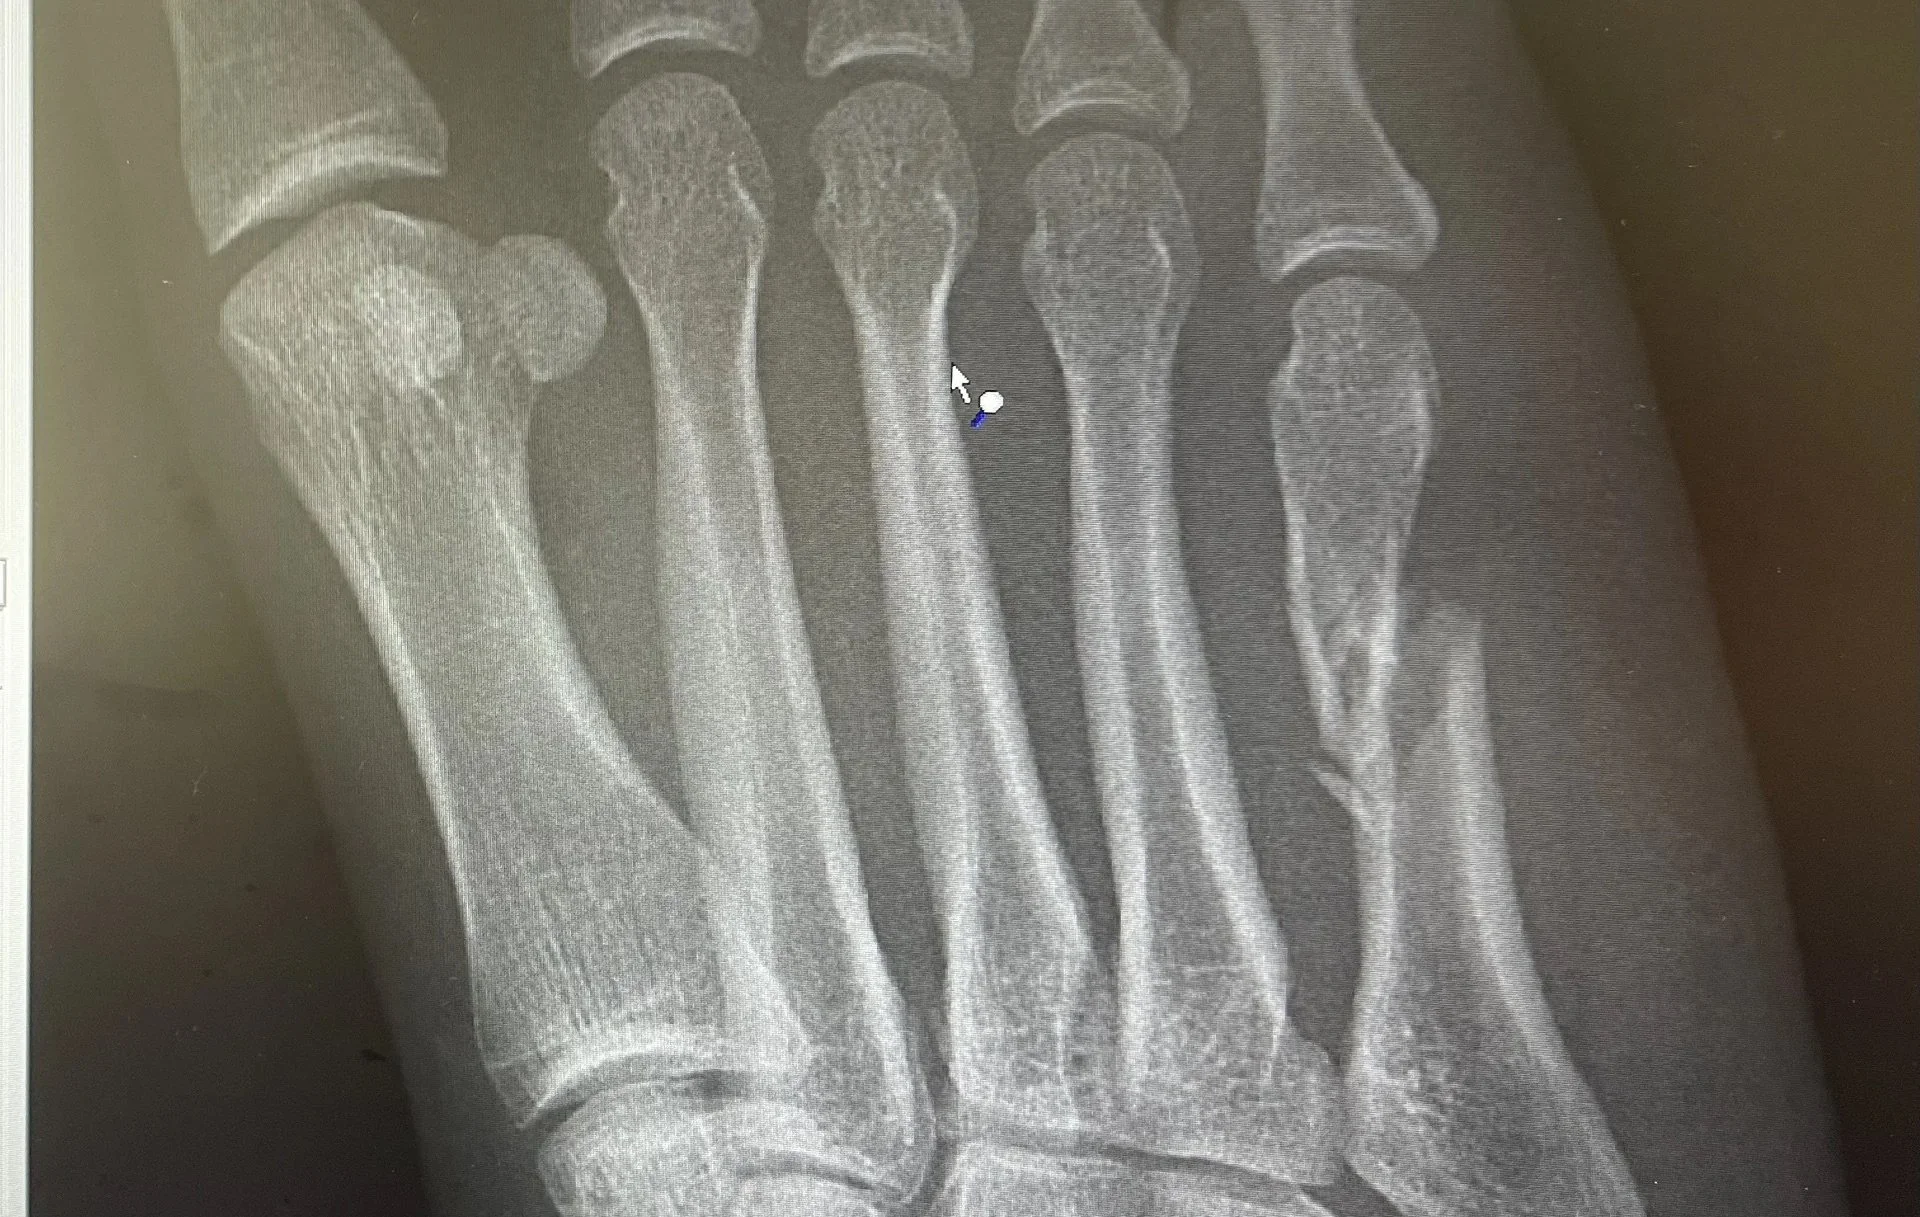

Imaging is used to confirm the diagnosis. X-rays typically identify the fracture location and allow classification into zones, which is critical for guiding treatment. Follow-up imaging may be obtained to assess healing progress.

Zone I fractures occur at the tuberosity of the fifth metatarsal and are often referred to as avulsion fractures. These injuries typically result from an inversion ankle injury and generally have a good blood supply, allowing them to heal reliably with non-surgical treatment.

Zone II fractures, commonly known as Jones fractures, occur at the metaphyseal-diaphyseal junction of the bone. This area has a relatively limited blood supply, which increases the risk of delayed healing or nonunion. These fractures require closer monitoring and may warrant surgical treatment in active individuals.

Zone III fractures occur farther along the shaft of the bone and are often associated with stress injuries or repetitive loading. These fractures carry the highest risk of delayed healing and nonunion and frequently require surgical intervention, particularly in athletes or patients with persistent symptoms.

Accurate identification of the fracture zone is essential, as it directly influences treatment recommendations, recovery time, and long-term outcomes.